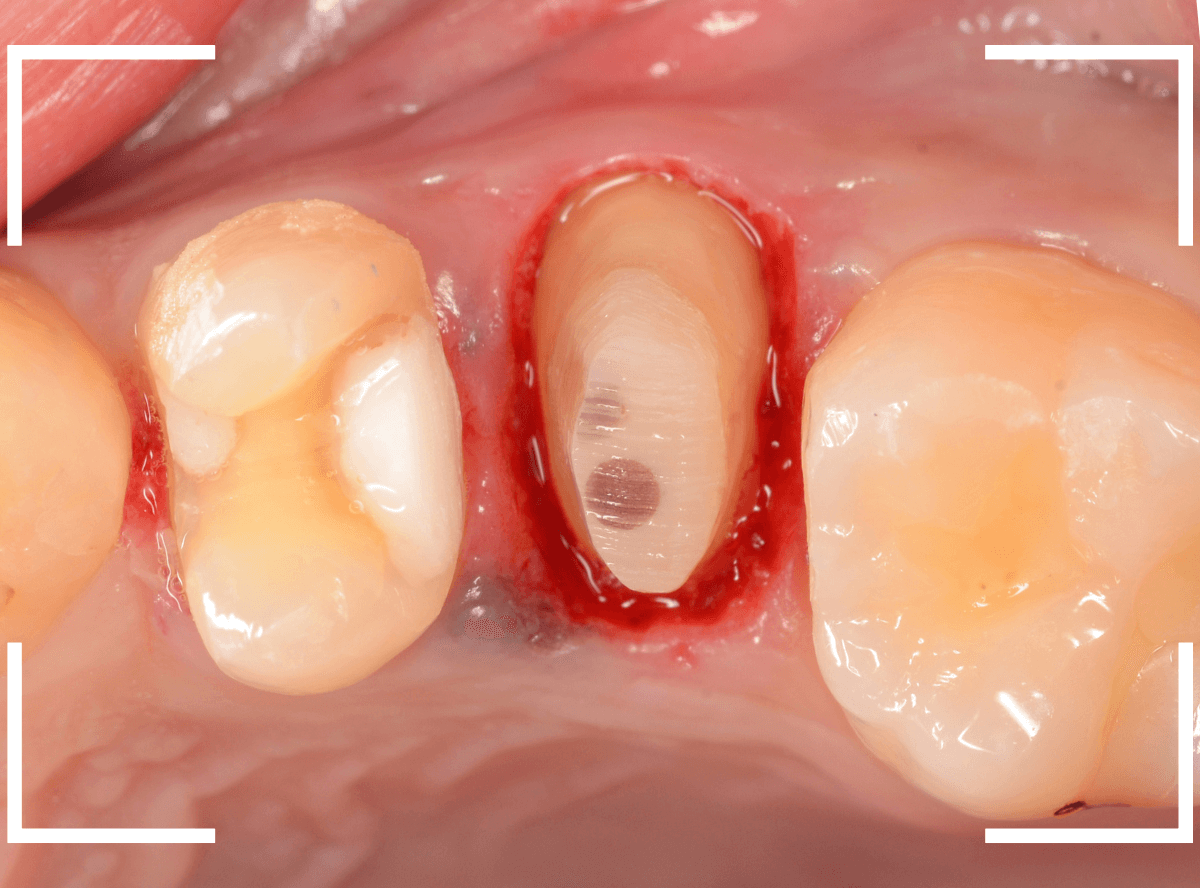

今回は、オール・ジルコニア・クラウンで製作することになりました。

最終setした状態です。

今回は厳しい条件でしたが、なんとか最終setまでする事ができました。

| 治療回数 | 5回 |

| 治療期間 | 6週間 |

| 費用 | オール・ジルコニア・クラウン (100,000円) +保険治療費用 |